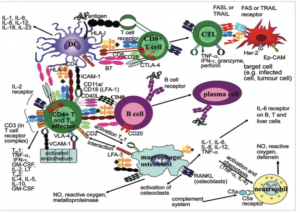

El viernes se analizarán las infecciones en dispositivos cardíacos y neuroquirúrgicos, y a continuación se celebrará una mesa redonda sobre infecciones complejas en pacientes inmunocomprometidos.